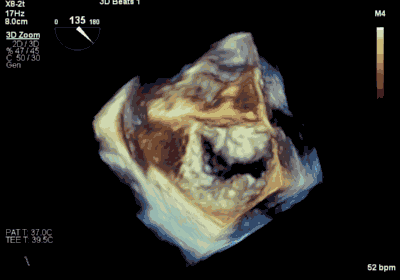

王焱、王斌教授团队通过术前和台北荣民总医院(Taipei Veterans General Hospital)宋思贤教授进行了详细的讨论并制定了最优的手术策略,同时术中视频连线获得宋思贤教授的技术支持,国产自拍 超声内科苏茂龙教授负责术中超声心动图引导。患者全麻以后,在经食道超声心动图和X射线引导下,经股静脉入路,将MitraClip瓣膜夹顺利送至二尖瓣前后叶交界中心处,成功捕捉二尖瓣前叶A2和后叶P2,经超声心动图反复确认瓣叶夹持牢固后,测定有效夹持长度11mm,评估反流量降至微量,释放瓣膜夹,超声心动图评估瓣膜夹位置和功能良好,测定左房压降至11/6mmHg,再次评估反流量仍为微量,手术顺利完成。

▲ MitraClip释放